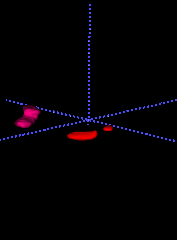

In this section, we are trying to explain the DeepLung by visualizing the nodule detection and classification results.

15.1 Nodule Detection

We randomly pick nodules from test fold 1 and visualize them in red circles of the first row in Fig. 14. Detected nodules are visualized in blue circles of the second row. Because CT is 3D voxel data, we can only plot the central slice for visualization. The third row shows the detection probabilities for the detected nodules. The central slice number is shown below each slice. The diameter of the circle is relative to the nodule size.

From the central slice visualizations in Fig. 14, we observe the detected nodule positions including central slice numbers are consistent with those of ground truth nodules. The circle sizes are similar between the nodules in the first row and the second row. The detection probability is also very high for these nodules in the third row. It shows 3D Faster R-CNN works well to detect the nodules from test fold 1.